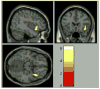

Previous neuroimaging studies of youth with bipolar disorder (BD) have identified abnormalities in emotion regulation circuitry. Using data from the Longitudinal Assessment of Manic Symptoms Cohort (a clinical sample recruited for behavioral and emotional dysregulation), we examined the impact of BD and medication on activation in these regions. Functional neuroimaging data were obtained from 15 youth with BD who currently were unmedicated with a mood stabilizer or antipsychotic (U-BD), 19 youth with medicated BD (M-BD), a non-bipolar clinical sample with high rates of disruptive behavioral disorders (non-BD, n = 59), and 29 healthy controls (HC) while they were shown task-irrelevant morphing emotional faces and shapes. Whole brain analysis was used to identify clusters that showed differential activation to emotion vs. shapes across group. To assess pair-wise comparisons and potential confounders, mean activation data were extracted only from clusters within regions previously implicated in emotion regulation (including amygdala and ventral prefrontal regions). A cluster in the right inferior frontal gyrus (IFG) showed group differences to emotion vs. shapes (159 voxels, corrected p < .05). Within this cluster, U-BD youth showed decreased activation relative to HC (p = .007) and non-BD (p = .004) youth. M-BD also showed decreased activation in this cluster relative to HC and non-BD youth, but these differences were attenuated. Results were specific to negative emotions, and not found with happy faces. IFG findings were not explained by other medications (e.g. stimulants) or diagnoses. Compared to both HC and a non-BD sample, U-BD is associated with abnormally decreased right IFG activation to negative emotions.